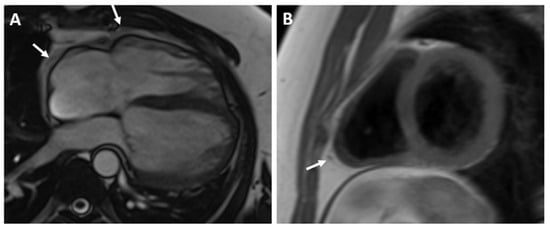

A 36-year-old male with first grade essential arterial hypertension with good medical control was referred for routine cardiovascular exam. He had a medical history of heart murmur since childhood and has been told to have interventricular communication. No prior medical records were submitted. Physical examination did not demonstrate any cardio-pulmonary abnormalities. An electrocardiogram (ECG) revealed sinus rhythm at 62 bpm, normal axis, poor R-wave progression in the precordial leads and repolarization abnormalities and negative T waves in V1–V4 (Figure 1).

Figure 1. ECG of the patient.